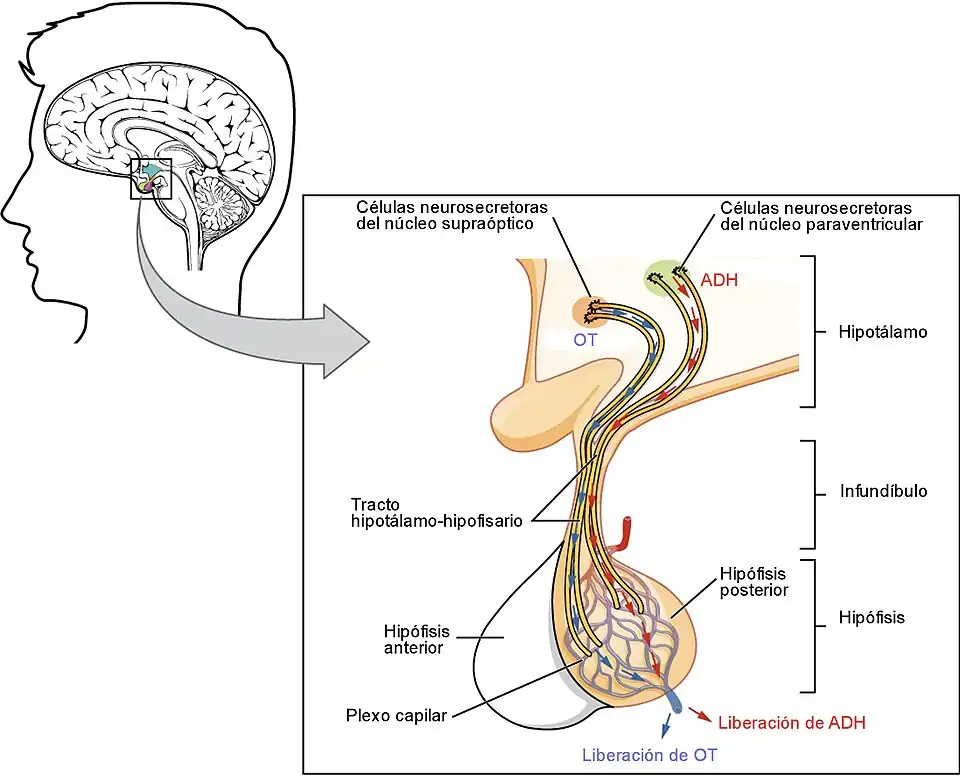

- Dos de ellas la hormona antidiurética y la oxitocina son producidas por las neuronas magnocelulares de los núcleos supraópticos y paraventriculares del hipotálamo, y se liberan directamente a la sangre, cuando llegan a la hipófisis posterior o neurohipófisis.

- Hormona antidiurética. El hipotálamo produce en el núcleo supraóptico y núcleo paraventricular[19] la hormona antidiurética (ADH), la cual se acumula en la neurohipófisis, desde donde es segregada. La vasopresina regula el balance de agua en el cuerpo actuando sobre los riñones.[20] La disfunción del hipotálamo en la producción de ADH causa diabetes insípida.[21]

- Oxitocina. La oxitocina es producida por el núcleo paraventricular del hipotálamo y almacenada y liberada por la neurohipófisis. Está relacionada con los patrones sexuales y con la conducta maternal y paternal. En las mujeres, la oxitocina se libera en grandes cantidades tras la distensión del cérvix uterino y la vagina durante el parto, así como en respuesta a la estimulación del pezón por la succión del bebé, facilitando por tanto el parto y la lactancia.[22] También se piensa que su función está asociada con el orgasmo, tanto en hombres como en mujeres.[23][24]

Neuronas magnocelulares

En los años 1950, las neuronas magnocelulares fueron las primeras caracterizadas como neurosecretoras.[44] Predominan en núcleo paraventricular y núcleo supraóptico, que sintetizan oxitocina y hormona antidiurética. Sus axones no mielinizados forman una estructura que atraviesa la eminencia media y llega a la neurohipófisis, donde se liberan las hormonas como respuesta a un potencial de acción.[36] Sin embargo, los axones también se proyectan hacia la médula espinal, la sustancia gris periacueductal y núcleos del rafé.[45]